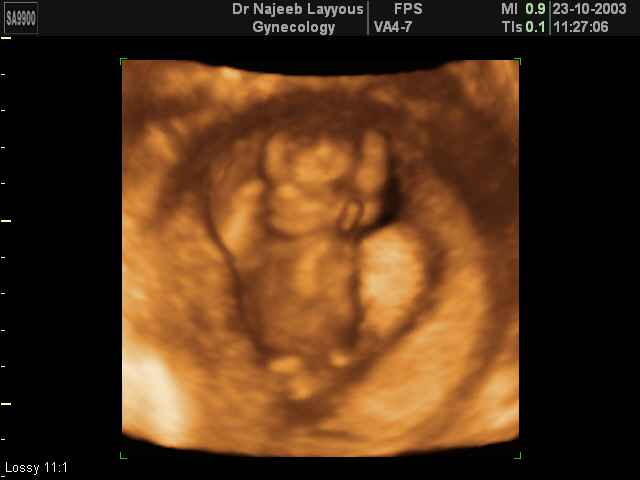

- First Trimester Ultrasound Photos

3D First Trimester Ultrasound Scan Photos ( Early Pregnancy Ultrasound Photos ) | Dr N Layyous